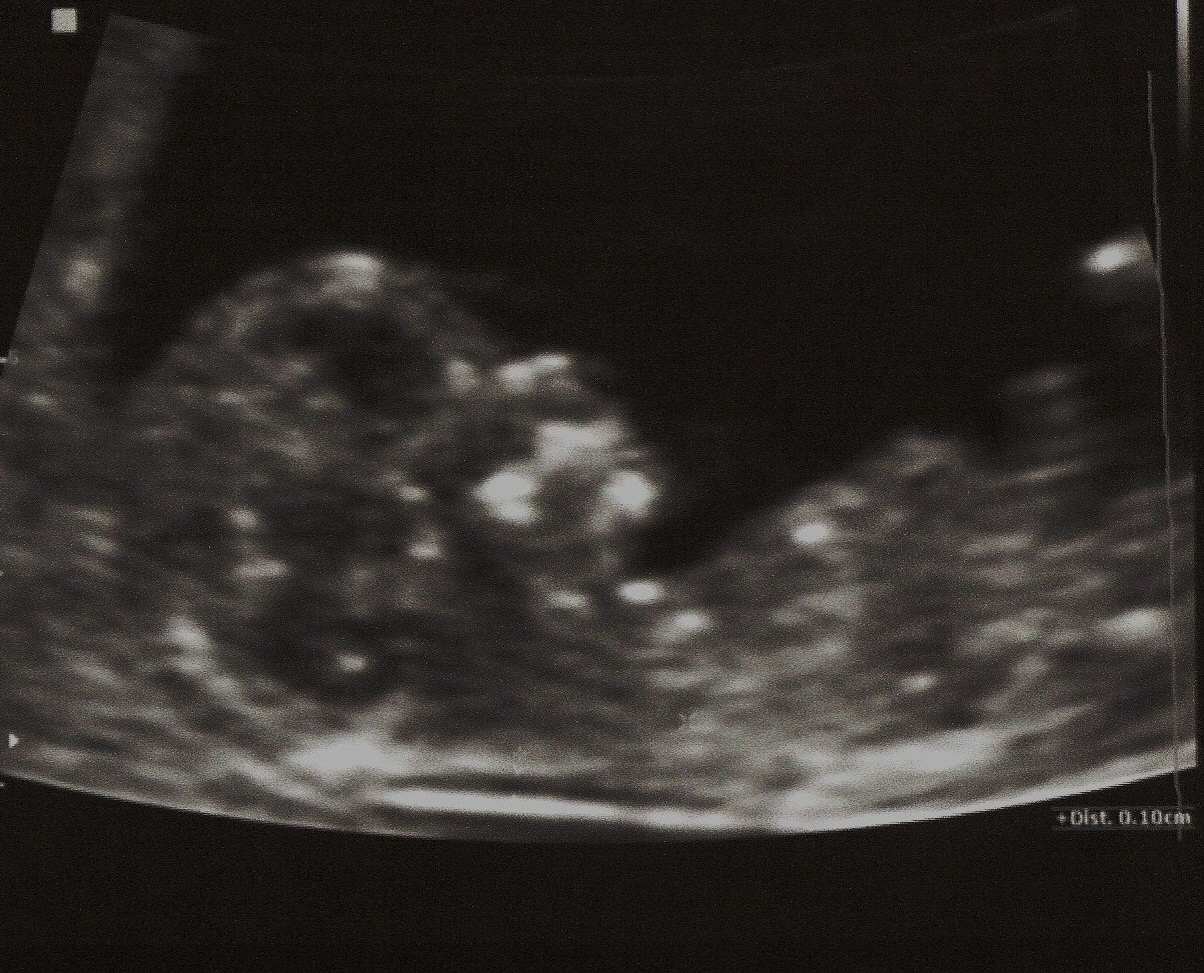

Mittels Ersttrimesterscreening ist es hingegen möglich, bei jeder Schwangeren eine individuelle Riskikoabschätzung für das Vorliegen einer Chromosomenstörung vorzunehmen. Hierbei wird zwischen 11 und 14 Schwangerschaftswochen eine Ultraschalluntersuchung durchgeführt mit genauer Messung der Breite eines Flüssigkeitsspaltes, der durch die Nackenhaut des Feten abgegrenzt wird (NT). Zusätzlich erfolgt eine Blutabnahme bei der Schwangeren, woraus 2 bestimmte Blutwerte (PAPP-A und free-beta-HCG) bestimmt werden, die ebenfalls in die Risikokalkulation eingehen.